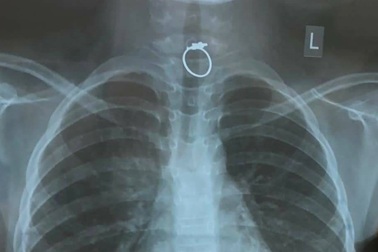

Nuốt chiếc nhẫn được tặng trong ngày Valentine bé gái phải cấp cứuThích thú với chiếc nhẫn được tặng, bé gái cầm chơi rồi bỏ vào miệng, cháu đã nuốt dị vật trong vô thức. Bệnh nhi phải nhập viện cấp cứu vì chiếc nhẫn kẹt ở thực quản.